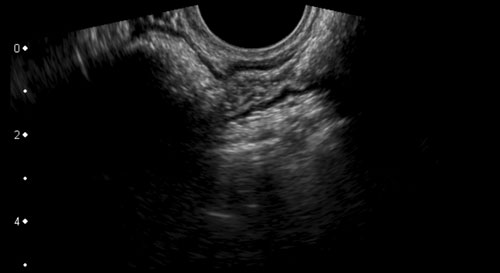

Hình ảnh giải phẫu TVUS của đại tràng sigma bình thường, có khả năng đè xẹp tốt, được khảo sát trên mặt cắt dọc và mặt cắt ngang.

Ở cuối chuỗi hình, trên mặt cắt ngang, đại tràng sigma dễ dàng bị đè xẹp bởi đầu dò (đầu mũi tên) áp vào xương cùng.